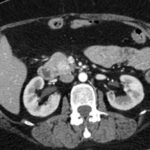

Paciente masculino de 35 años de edad, con antecedentes de tabaquismo, etilismo, consumo de sustancias psicoactivas. Ingresa al hospital de Sanatorio Franchin el 24 de mayo de 2024, donde se constata hipoglucemia severa con buena respuesta al glucosado hipertónico endovenoso. Al examen físico con la típica tríada de Whipple, dado por síntomas neuroglucopénicos de alteración del estado de conciencia, glucemia de 25 mg/dl y alivio sintomático después de la administración de glucosa. El paciente recupera el estado de conciencia y refiere dolor abdominal a nivel de epigastrio, por lo que se le realiza ecografía abdominal, donde se evidencia lesión nodular hipoecogénica en cuerpo del páncreas. Por esta razón se pasa al paciente a tomografía, donde se constata una formación nodular a nivel del cuerpo del páncreas, que presenta un ávido realce en fase arterial con homogeneización de la lesión en tiempo tardío.

Ahora bien, como se mencionaba al principio, el estudio ecográfico es de muy baja sensibilidad y se identifique o no la lesión por este estudio, nuestro siguiente paso en el algoritmo diagnóstico de esta lesión es la tomografía. Esta es la prueba no invasiva inicial, con una sensibilidad del 63% al 83%, y detecta del 70% al 80% de los tumores. Esta debe realizarse como un estudio trifásico: fase arterial temprana a los 30 segundos, fase venosa a los 70 segundos, fase tardía de 3 a 5 minutos. La característica de estos tumores por tomografía es que se presentan como una masa sólida que tiene un ávido realce en la fase arterial, cuyo realce se mantiene y se observa más tenue en la fase venosa y en los tiempos tardíos la lesión se homogeniza.

Para mi caso, y dando una visión general de los métodos de imagen no invasivos en esta revisión retrospectiva, solo a uno de los pacientes se le detectó la lesión por ecografía, donde se visualizó una lesión nodular hipoecogénica en el cuerpo del páncreas. A los demás pacientes se les detectó la lesión por tomografía en estudio trifásico, donde resaltan las características ya descritas por la literatura de lesiones hipervasculares con intenso realce en fase arterial, localizadas en diferentes partes del páncreas, como cabeza, cuerpo y cola.